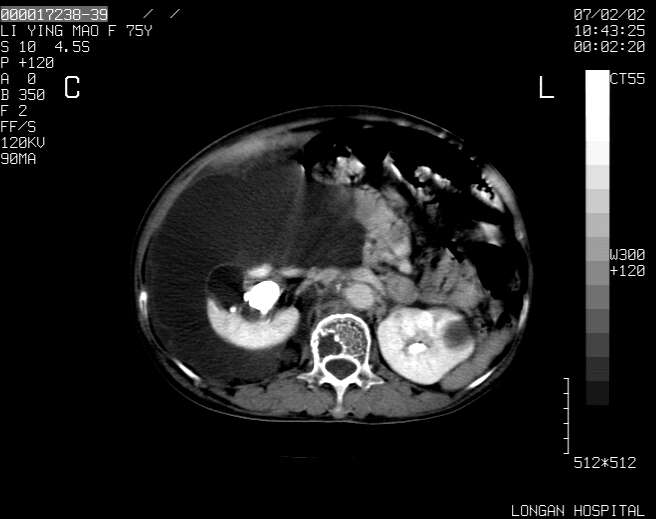

以下是引用dyqct在2007-2-10 8:53:00的发言:[br]考虑:1、肝脏多发囊肿[br] 2、左肾囊肿,右肾多发结石并积水。[br] 3、右胸少量积液。[br] 4、右肾周包裹性积液或淋巴管瘤(有见缝就钻的征象、薄隔、小结节状钙化)?[br] 5、腰椎动脉瘤样骨囊肿?[br] [br] [br]